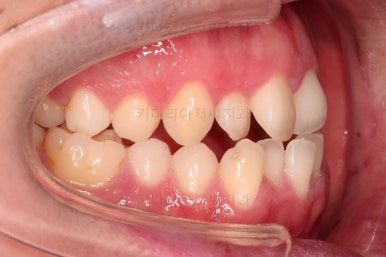

초진 시 입안의 모습입니다.

교합이 많이 안좋습니다.

위아랫니가 서로 엇갈려 가며 지그재그로 껴 들어가야 어금니 맞물림이 생기는데요.

이번 환자분은 아랫니, 아래턱이 전반적으로 앞으로 나와 있어서 교합이 전혀 안되고 있는 상태였습니다.